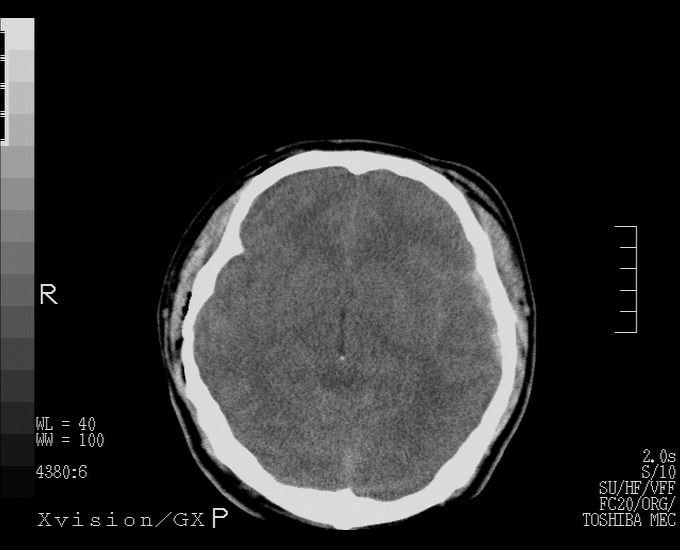

以下是引用随光逐影在2010-4-11 11:00:00的发言:[br]1)左侧额颞顶部硬膜下血肿。2)蛛网膜下腔出血。3)右侧颞顶部颅骨线形骨折。[br][br]20小时后复查:左侧额颞叶脑挫裂伤;左侧额颞顶部硬膜下血肿及蛛网膜下腔出血有吸收表现;右侧颞顶部颅骨线形骨折。[br]